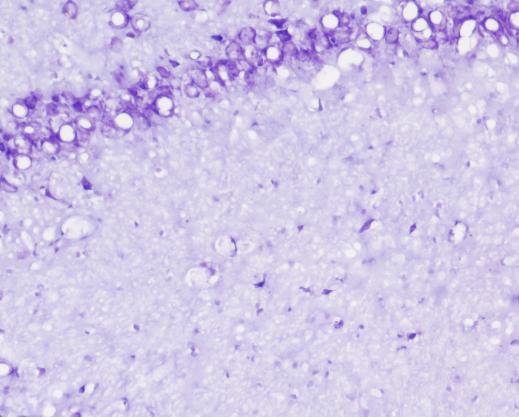

10、尼氏染色实验结果(小鼠脑组织海马区焦油紫法举例)

尼氏染色实验结果解读:小鼠脑组织内的尼氏小体被焦油紫着色为深紫色或者紫蓝色,背景色接近无色或者淡紫色。